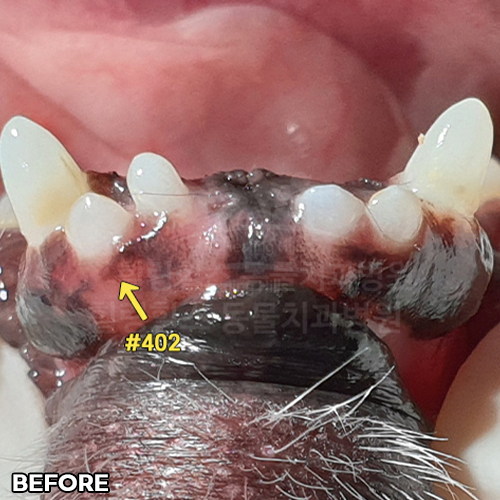

강아지송곳니치주염 치료하고 자라난 잇몸뼈, 빨갛게 부은 잇몸이 좋아진 모습 - 5개월 뒤 덴탈씨티로 확인!